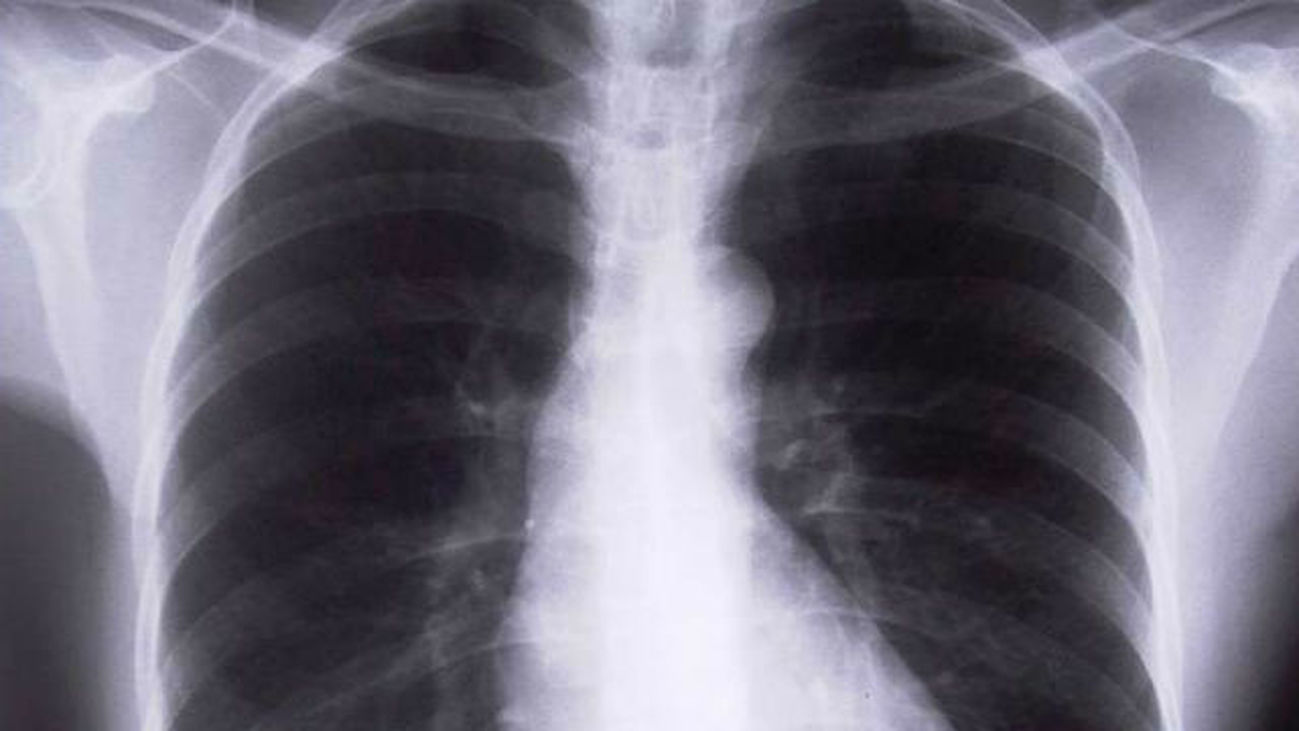

El carcinoma de pulmón, el tipo de cáncer que más muertes causa en el mundo, tiene los días contados Hoy en Madrid Matinal El carcinoma de pulmón, el tipo de cáncer que más muertes causa en el mundo, tiene los días contados